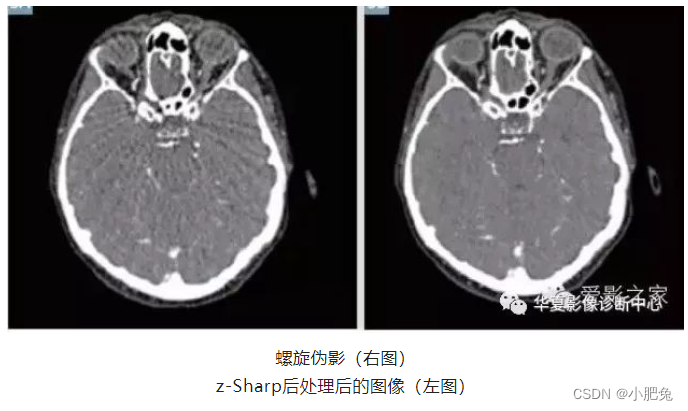

亦称做风车状伪影。CT系统采集的数据来自于有限的探测器通道。螺旋CT重建算法需要在z方向上插值以获得轴位平面投影。与用理想无限精确网格采集的数据相比,有限数据插值会在高对比度物体处,比如骨骼等,不可避免地引入误差。伪影表现为在高密度物体附近的风车状伪影,并且当沿轴向翻阅图像时出现伪影绕中心旋转的现象。